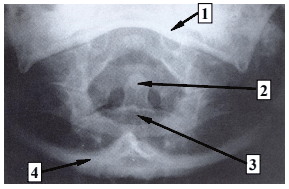

A imagem acima corresponde à incidência do Método de